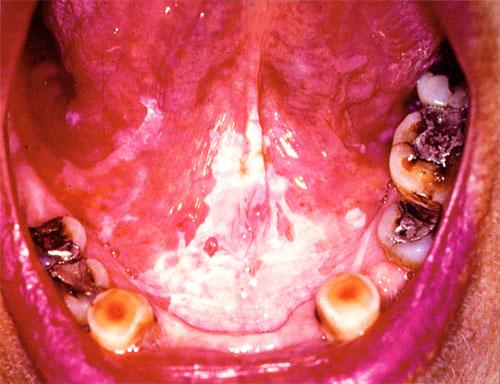

Leukoplakia is a clinical term that refers to a predominantly white lesion of the oral mucosa that cannot be rubbed off or characterized by any other definable lesion or known disease.130 Leukoplakia is the most common precancerous lesion of the oral mucosa, with the potential to become oral SCC (OSCC).131 Oral leukoplakia (OL) is in the same clinical spectrum of disease as oral erythroplakia (OE), but unlike OE it is a much more frequently diagnosed lesion with a much lower rate of malignant transformation.

OL is clinically divided into two sub-types: homogeneous OL and non-homogeneous OL. Homogeneous OL has been defined as a mostly white, flat, uniform lesion that may have shallow cracks and a smooth, wrinkled, or corrugated surface that is consistent throughout.137 Non-homogeneous OL has been defined as a mostly white or white and red lesion (erythroleukoplakia) that may be either irregular and flat, nodular (speckled), ulcerative, or verrucous. Non-homogeneous OL purportedly has a risk of malignant transformation that is four to five times higher than that of homogeneous OL. Another clinical sub-type of OL is proliferative verrucous leukoplakia, whichis most often found in patients who do not use tobacco products. This sub-type has a high rate of transformation to malignancy.